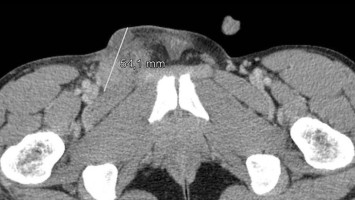

HPV-positives Oropharynxkarzinom – eine Gefahr für den Partner?

Bei einer 58-jährigen Patientin wird ein HPV-positives Plattenepithelkarzinom des Oropharynx erfolgreich therapiert. Knapp drei Jahre später stellt sich ihr inzwischen 70 Jahre alter Ehemann mit einem Druckgefühl des Halses rechts vor...